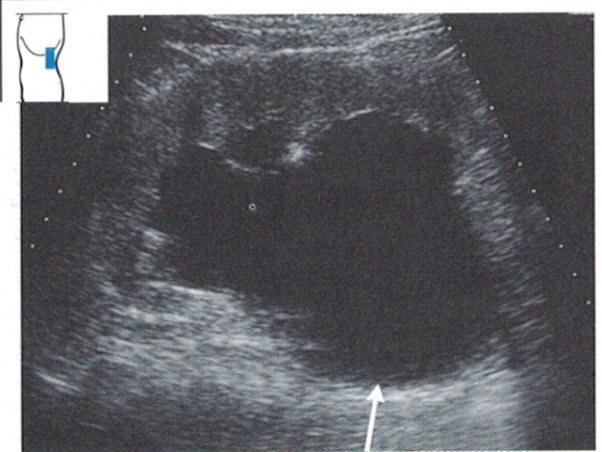

Ingresa en Unidad de Críticos hemodinámicamente estable. En analítica sanguínea: empeoramiento de función renal con fracaso renal agudo AKIN III, urocultivo (flora mixta) y hemocultivos (negativos). Se realiza ecografía abdominal urgente: ureterohidronefrosis grado III bilateral. La paciente ingresa a cargo de Urología, precisando sondaje y colocación de pesario. Tras dos semanas es dada de alta.

La demora diagnóstica en esta paciente fue de 6 horas. Es habitual la saturación de los Servicios de Urgencia Extrahospitalarios, por lo que es imprescindible un correcto triaje para priorizar la atención sanitaria. En este medio, obtener correctamente los datos de la historia clínica es fundamental ante la limitación de pruebas diagnósticas disponibles. Entre ellas, la utilización de la ecografía clínica podría haber sido de gran ayuda para emitir un correcto diagnóstico diferencial, y en consecuencia administrar el tratamiento y/o remitir al recurso más adecuado.

En definitiva, la ecografía es una herramienta fundamental para los Médicos de Familia, tanto en consulta como en urgencias, al reducir la incertidumbre y disminuir los tiempos diagnósticos.